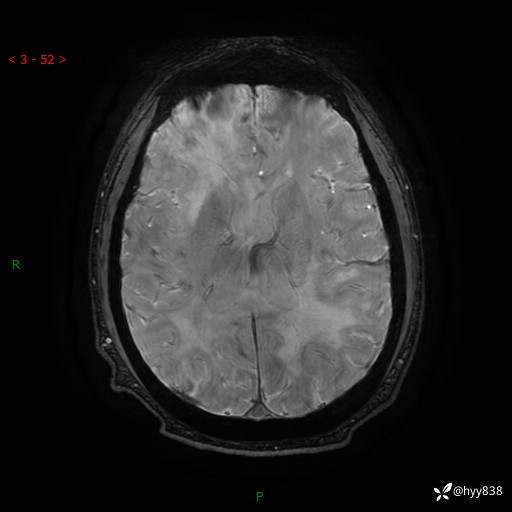

磁敏感成像